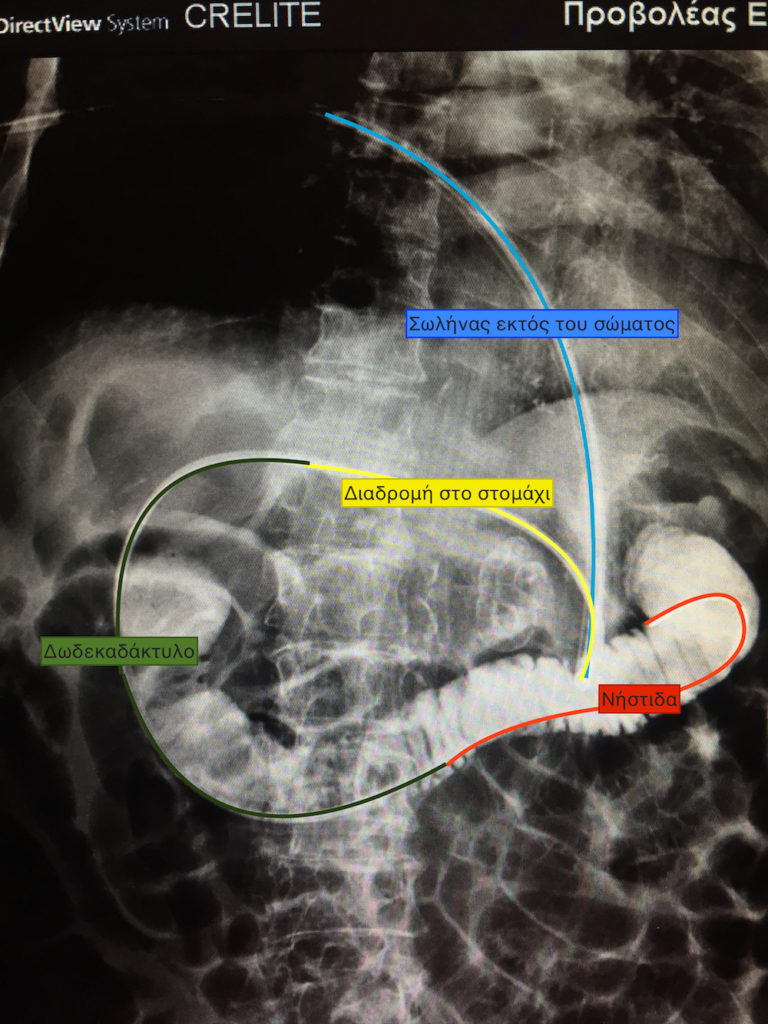

Δύο περιπτώσεις ενδοσκοπικής επανατοποθέτησης γαστρονηστιδικών σωλήνων, σε ηλικιωμένους ασθενείς που είχαν απλές γαστροστομιες και κινδύνευαν από επανειλημμένες εισροφήσεις τροφών, οι οποίες ανέβαιναν με αναγωγές προς το λαιμό και εισχωρούσαν στους πνεύμονες.

Οι αντικαταστάσεις των σωλήνων έγιναν λόγω φθοράς των υλικών.

Η πρώτη περίπτωση αφορά άνδρα ηλικίας 95 ετών. Τα τελευταία 6 χρόνια σιτίζεται με γαστρονηστιδικό σωλήνα και δεν έχει κανένα αναπνευστικό πρόβλημα.

Η δεύτερη περίπτωση είναι γυναίκα 74 ετών. Τα τελευταία 2,5 χρόνια σιτίζεται με γαστρονηστιδικό καθετήρα, χωρίς προβλήματα πλέον με εισροφήσεις υγρών.